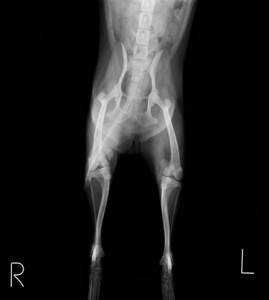

主訴:3ヶ月前から右後肢を着地しないで上げるようになっており、近医で痛み止めやサプリメントを処方されましたが、最近反対側の左後肢も足を曲げたまま歩けなくなったとのことで近医からのご紹介で来院されました。来院時、両後足とも屈曲したまま歩行できす、足を伸ばすこともできない状態でした。レントゲン検査にて左右とも膝蓋骨が内方に脱臼し、元に戻らない状態の上、大腿骨と脛骨が重度に変形していました。

左右とも膝蓋骨の内方脱臼および大腿骨、脛骨の変形が認められます。 まだ子犬で、今のままではこの状態のままずっと歩けなくなることは間違いないと判断し、飼い主様とご相談し、両側膝蓋骨内方脱臼整復手術および、変形が強い右の大腿骨矯正骨きり手術を行いました。